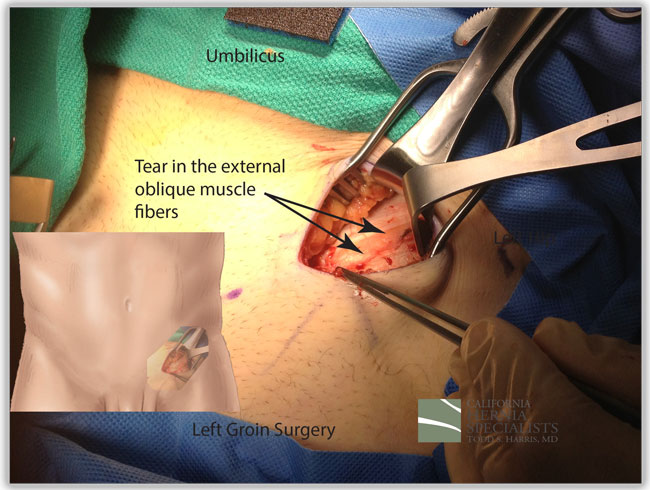

This patient had almost 6 years of left groin pain. He was an avid athlete and had felt a ‘tear’ in his left groin. Ultrasounds and CT scans failed to show an inguinal hernia however his pain continued. Over the years, the pain got worse and traveled further up and down his groin.

Ultimately he sought help at California Hernia Specialists where a tentative diagnosis of a sports hernia was made based on his symptoms. No inguinal hernia could be felt on examination before surgery.

The intra-operative photo above shows an obvious tear in the external oblique, which is the outer layer of muscle in the groin. In the photo, the yellow fat from underneath the muscle is seen between two edges of the white muscle fascia which have torn. The tear was about 4 inches long, and about a 0.5 inch wide. This was repaired with a mesh under the tear, and by closing the tear with sutures.

The photo below shows a normal external oblique which is white throughout with no yellow of fat from underneath and no tear.

On recent follow-up, the patient is having no more pain in his left groin and is back to elite athletic activities on a full time basis.